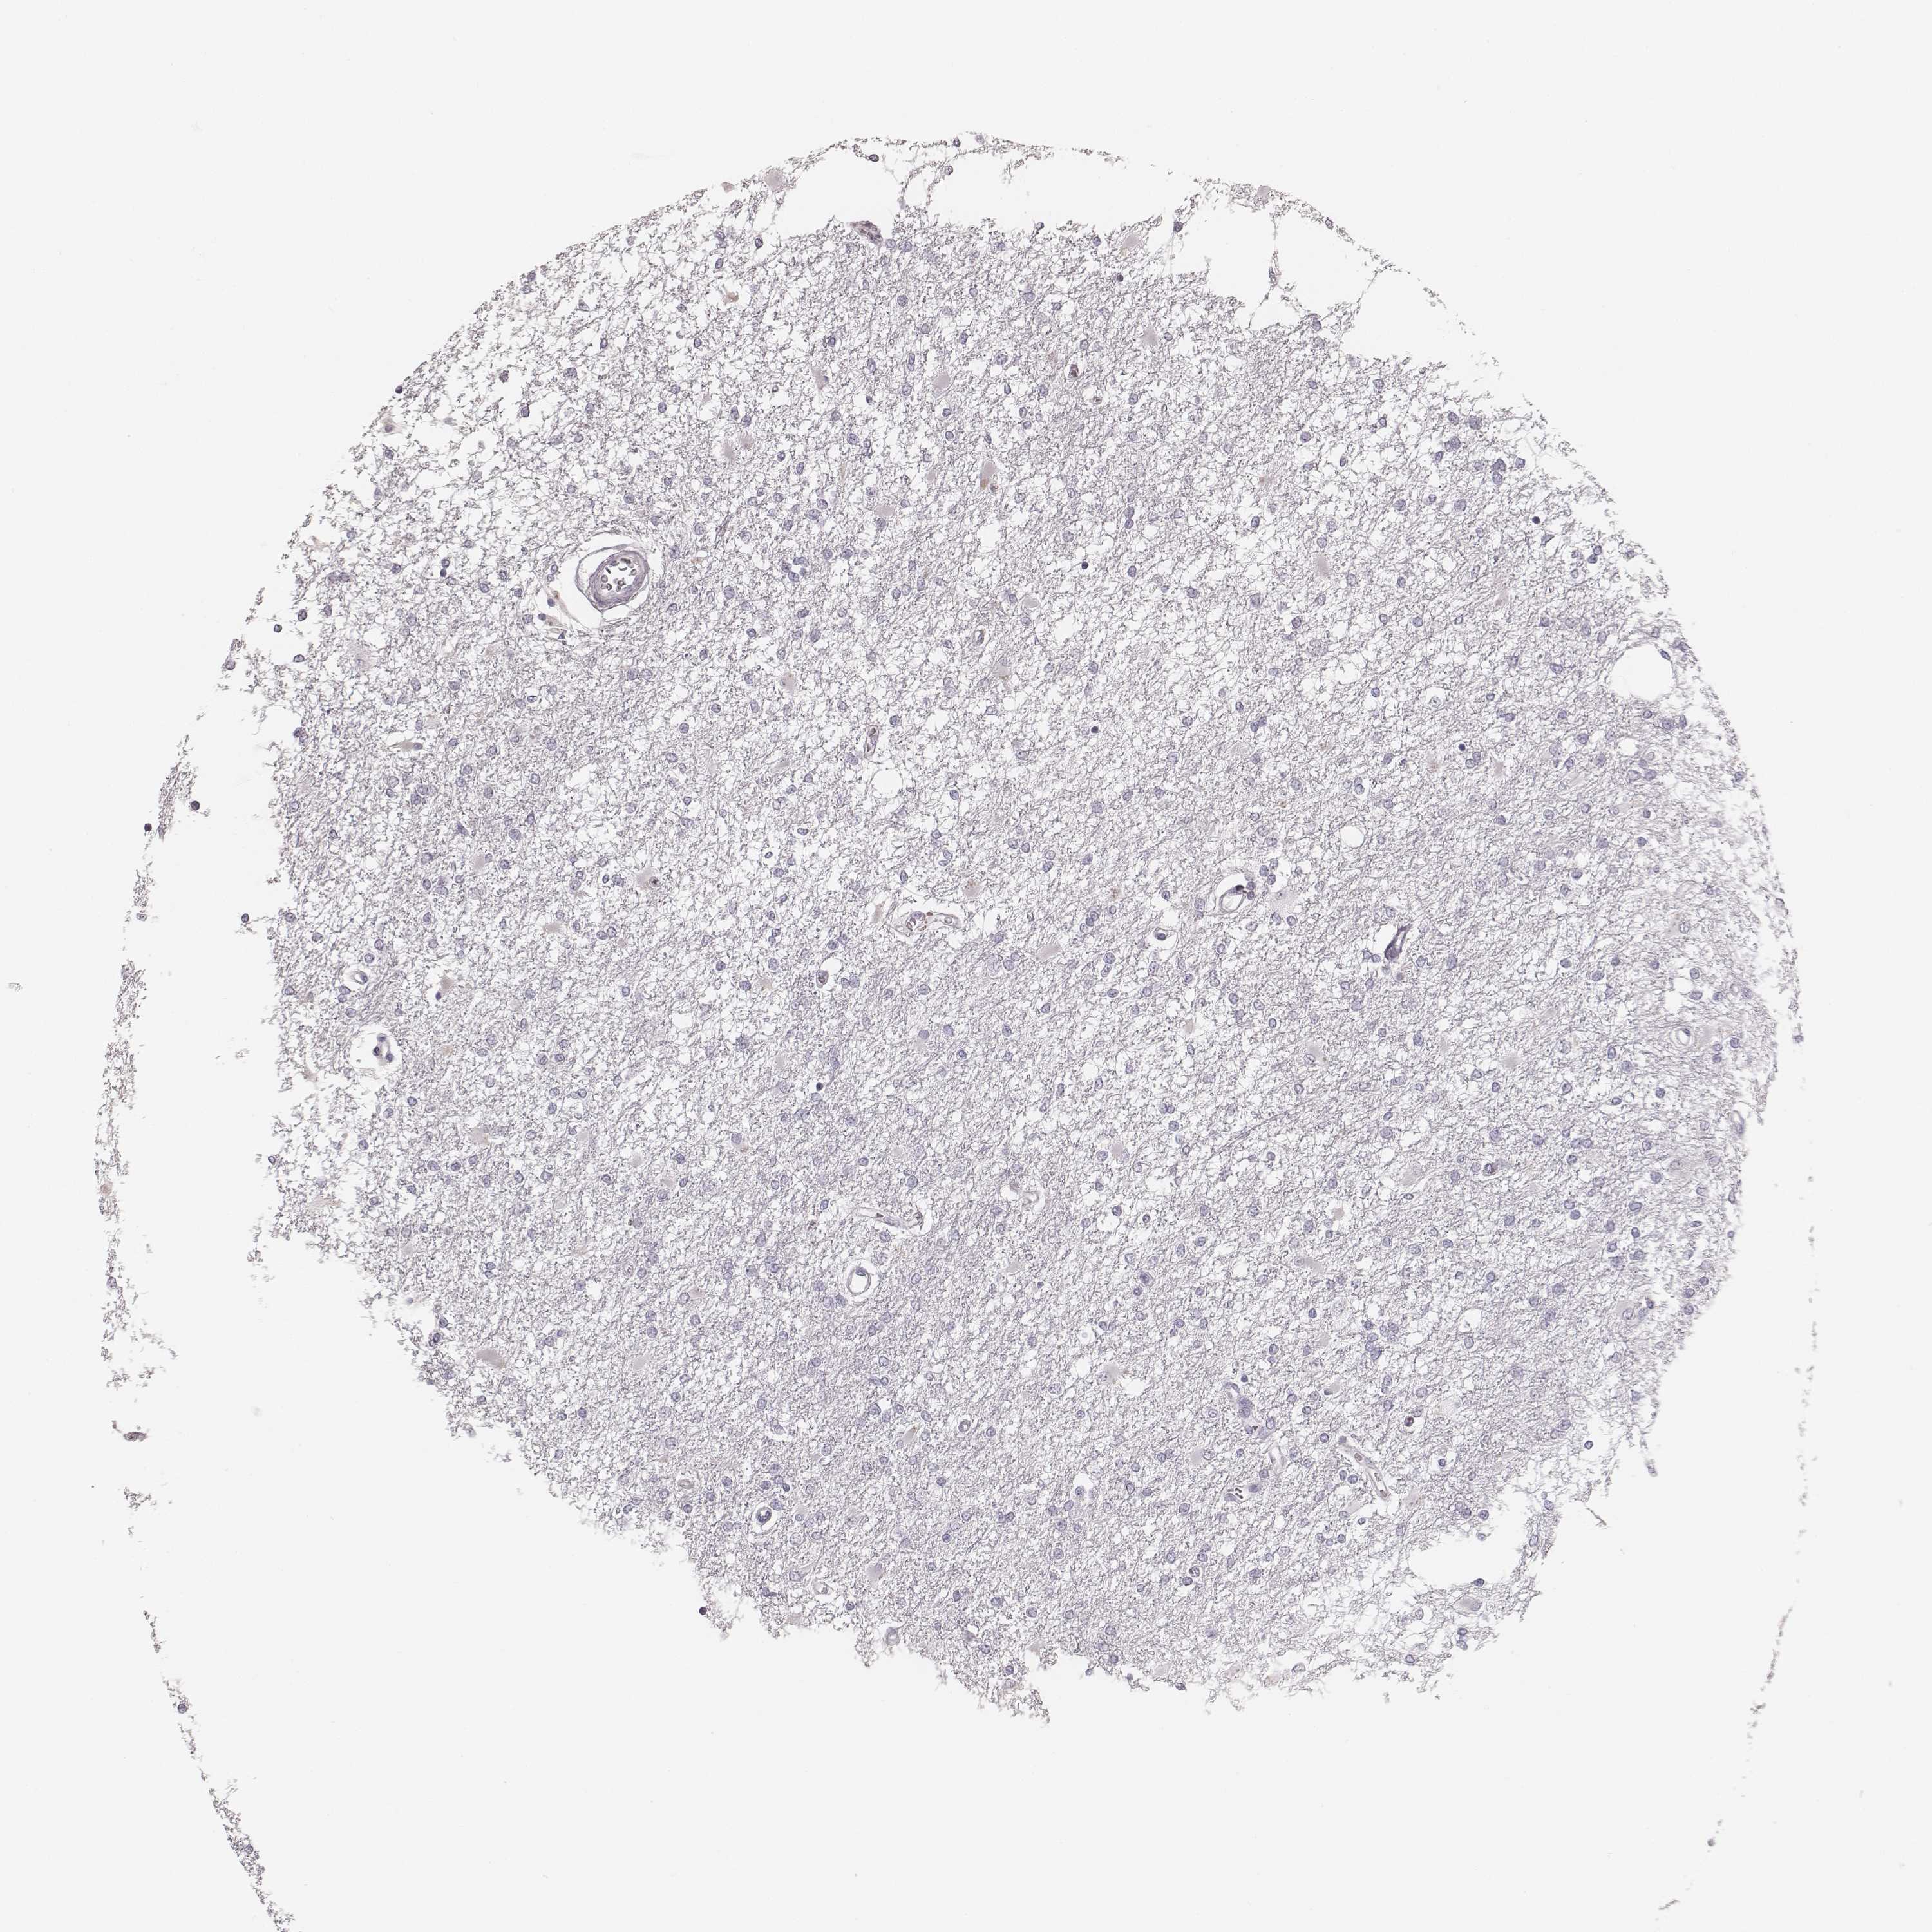

GLIOMA - Protein expressioni

A mouse-over function shows sample information and annotation data. Click on an image to view it in a full screen mode. Samples can be filtered based on level of antibody staining by selecting one or several of the following categories: high, medium, low and not detected. The assay and annotation is described here.

Note that samples used for immunohistochemistry by the Human Protein Atlas do not correspond to samples in the TCGA dataset.

Antibody stainingi

Antibody staining in the annotated cell types in the current human tissue is reported as not detected, low, medium, or high, based on conventional immunohistochemistry profiling in selected tissues. This score is based on the combination of the staining intensity and fraction of stained cells.

Each image is clickable and will lead to virtual microscopy that enables deeper exploration of all samples and also displays staining intensity scores, fraction scores and subcellular localization as well as patient and tissue information for each sample.

Antibody HPA051929

Staining

High

Medium

Low

Not detected

Intensity

Strong

Moderate

Weak

Negative

Quantity

>75%

75%-25%

<25%

None

Location

Nuclear

Cytoplasmic/membranous

Cytoplasmic/membranous,nuclear

Glioma, malignant, Low grade

Glioma, malignant, High grade

Glioma, malignant, NOS